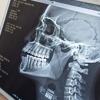

Repositorio bibliográfico de Ortodoncia, diseñado para estudiantes de la especialidad. Contiene recursos fundamentales sobre diagnóstico, biomecánica y tratamiento de maloclusiones. Incluye artículos científicos, manuales, casos clínicos y guías de práctica que apoyan el desarrollo académico y clínico en la corrección de alteraciones dentofaciales.